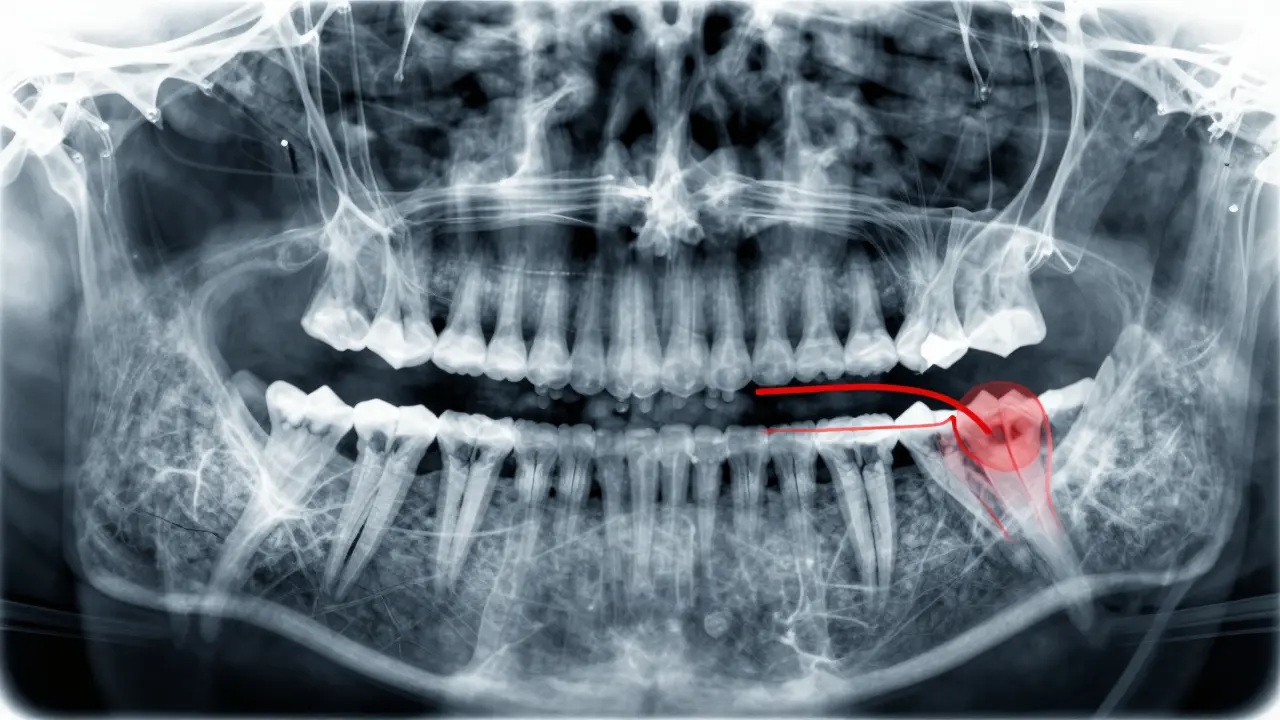

Panoramatický rentgen ukazuje zastíněné moudraky tlačící na sousední zub.

Nejčastěji se používá panoramatický rentgen - jedna snímka, která ukáže všechny zuby, čelisti, klouby a moudraky najednou. Na něm je vidět:

• Je moudrak úplně zastíněný v kosti?

• Roste šikmo? Do které strany?

• Tlačí na sousední zub?

• Je kořen už vytvořený? Nebo ještě roste?